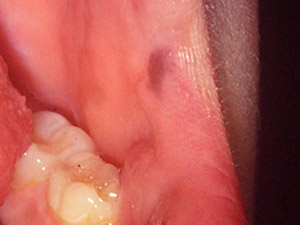

Nevus

The nevus, colloquially known as mole or birthmark, is an either congenital or acquired malformation of the skin, representing a benign neoplasm of cutaneous melanocytes.

Melanocytic nevi are sharply defined, vary greatly in shape (but are symmetric), are uniformly coloured and appear commonly as slightly raised papule. The intramucosal nevus represents the most frequent subtype of the nevi. It is brown in colour and most often found in the buccal mucosa. The similarly common blue nevi are most frequently located on the hard palate.

The majority of nevi develop on the skin, making the oral mucosa a rather rarely affected area. The average age of affected humans is 38 years. Rare cases of nevi turning into malignancy are reported. back